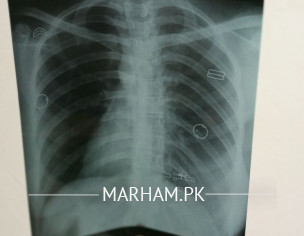

Kindly do comment on chest x-ray of my sister

normal

ulti tasveer hy

seems normal